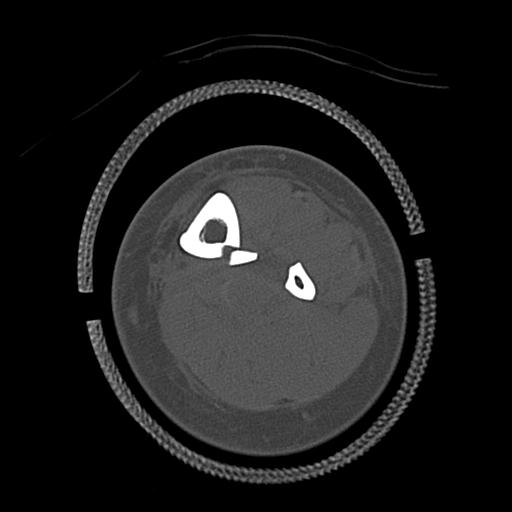

91983 11/16 左膝 2R 11/18 2R 55歳男性 脛骨骨切り術